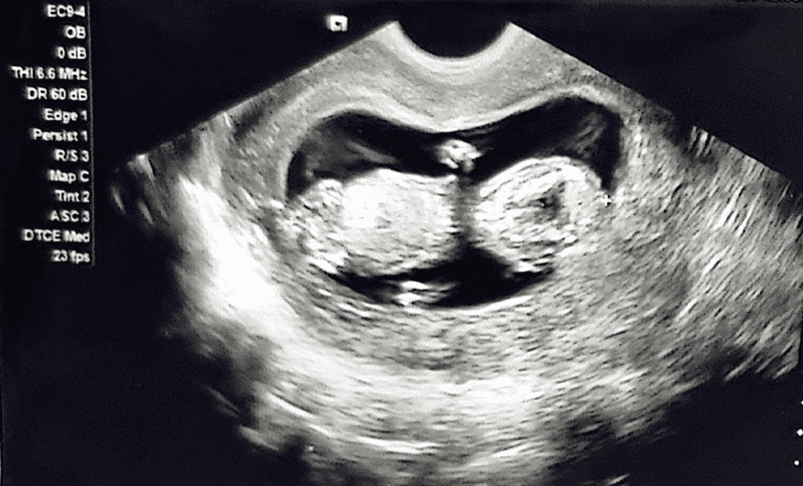

28-year-old female G7P3+0+3+3 12+4 weeks of gestation previously healthy with no known medical or surgical history presented to the outpatient department for her regular antenatal follow up. During her first visit she mentioned that she is having difficulties in passing urine. Baseline investigations including complete blood count (CBC), renal function test (RFT), urine routine and culture were done to look for urinary tract infection which was ruled out. However, the patient was given an ultrasound appointment to look for any underlying urinary tract pathology along with urology outpatient clinical referral. However, patient came after few days with worsening symptoms leading to complete urinary retention thus the patient admitted to the hospital and Foleys catheter was inserted. Our differential diagnosis was the following: Urinary tract infection, Urinary tract obstruction attributed to a urological cause i.e. nephrolithiasis or attributed to a gynecological cause i.e. large uterine fibroid. During hospital stay urine culture was repeated which came back with no growth. An Ultrasound was done by an obstetrician which revealed an acutely retroverted uterus with a fetus matching gestational age calculated from the first day of her last menstrual period (LMP) as shown in Figure 1 and 2.

Figure 2: Transvaginal ultrasound revealing an acutely retroverted incarcerated uterus with a viable fetus matching 12 weeks of gestation